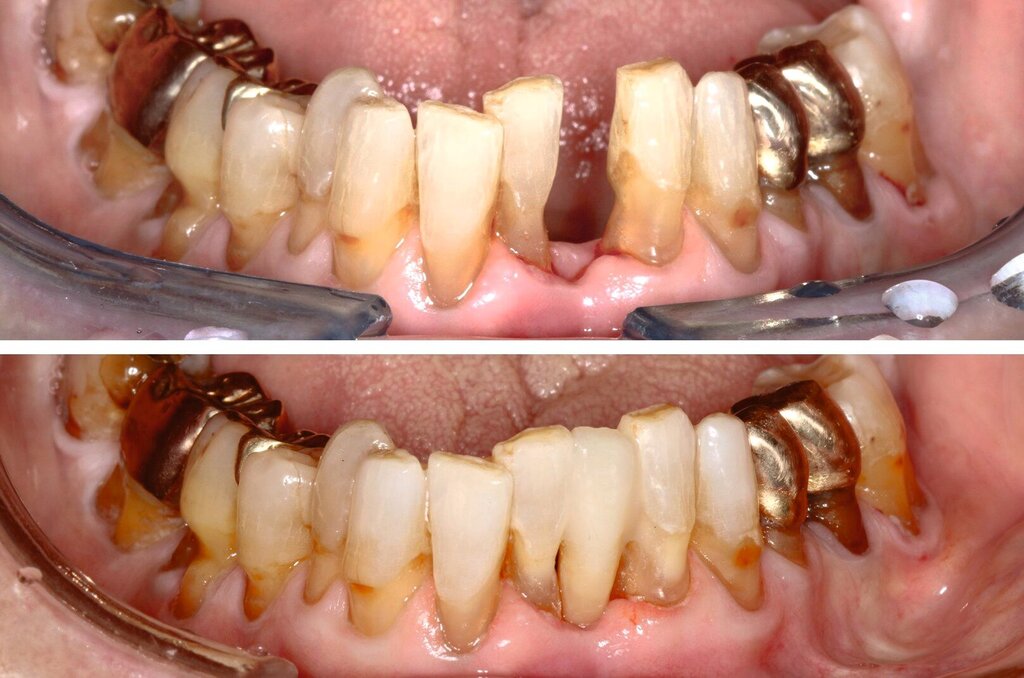

Obwohl die unterstützende Parodontitistherapie (UPT) vier Jahre unterbrochen war, konnte bis auf einen Grad III gelockerten Zahn 31 und eine Grad I–II gelockerte, restliche Unterkieferfrontbezahnung ein gut erhaltenes Gebiss festgestellt werden. Dies ist auch darauf zurückzuführen, dass die Patientin – trotz ihres fortgeschrittenen Alters – die häusliche Mundhygiene stets sehr gründlich betrieb, wie auch aus früheren Akteneinträgen ersichtlich wurde (Abbildung 4).

Allgemeinanamnestisch zeigte die Patientin neben einer diagnostizierten Herzinsuffizienz, einer medikamentös behandelten, stabilisierten Angina pectoris und einer Niereninsuffizienz auch eine fortgeschrittene Wirbelsäulenarthritis, wodurch längeres, nach hinten gelehntes Sitzen auf dem Behandlungsstuhl für die Patientin schmerzhaft war und ihre Adhärenz für längere Sitzungen deutlich reduzierte.